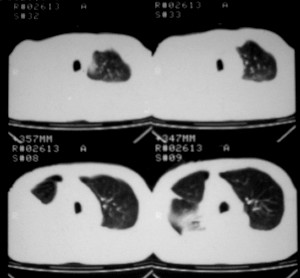

m ,60岁,右上肺ca术后一月。

纵隔淋巴结增大,双侧胸水。考虑术后残留,而非复发。

1、右肺癌术后改变。2、双侧胸水、腹水。3、多发性肝囊肿,右侧肾囊肿。

肺癌术后 。双侧胸水 纵隔 胸膜 肝脏转移